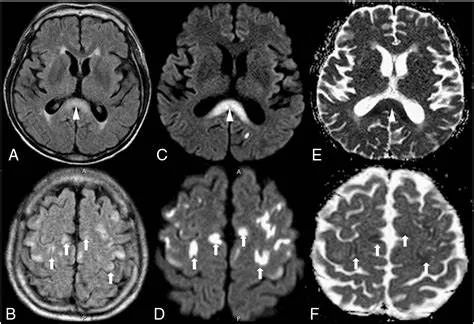

胼胝体压部病变及多发皮层对称性病变,表现为扩散受限